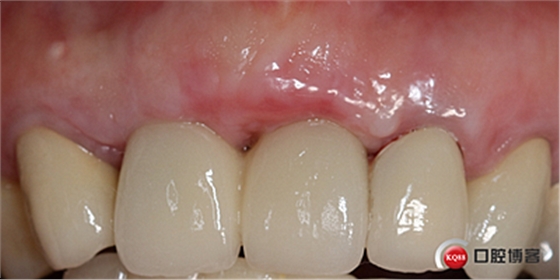

戴牙后半年復查。